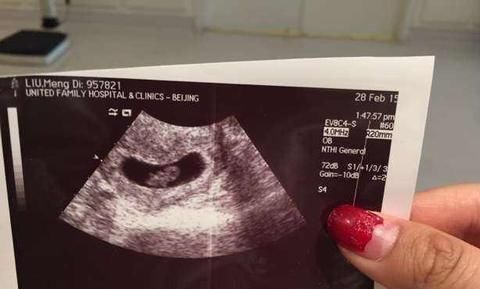

怀孕后7-8周时,孕妈妈要去医院做第一次产检,这次的主要任务是检查有没有胎心胎胎芽。有的孕妈妈很顺利,胎心胎芽都看到了。但是有的孕妈妈却为结果感到难过,当时没有看到胎心胎芽。医生的解释并不一样,有的说胚胎没长好,做好流产准备吧,有的医生却说过一周再来检查一下,说不定就有了。

孕妈妈一般都不会甘心,好不容易怀上孕,一定要看到好的结果,一般会选择再过一段时间去检查一次,其中有一个孕妈妈到怀孕10周才看到胎心胎芽。看上去有些夸张,但事实确实如此。

孕妈妈们就纳闷了,为什么胎心胎芽出现的时间早晚不一样呢?有的7周就很明显,有的则要等到10周。这和孕妈妈以及胚胎都有一定的关系。

怀孕5周时,胚胎开始变身,分化成内、中、外三个胚层,不同的胚层将来分化成不同的结构或者器官,其中中胚层分化成循环系统,心脏开始成形,并且有了搏动,每分钟搏动70次。但是只有6mm,太微小,B超不容易判断。

怀孕7周时,心脏已经划分成左心房和右心室,开始有规律的跳动,每分钟跳150次,开始有血液循环。

所以,从理论上来说,怀孕7-8周做B超是能看到胎心和胎芽的,如果没看到一定是有原因的。